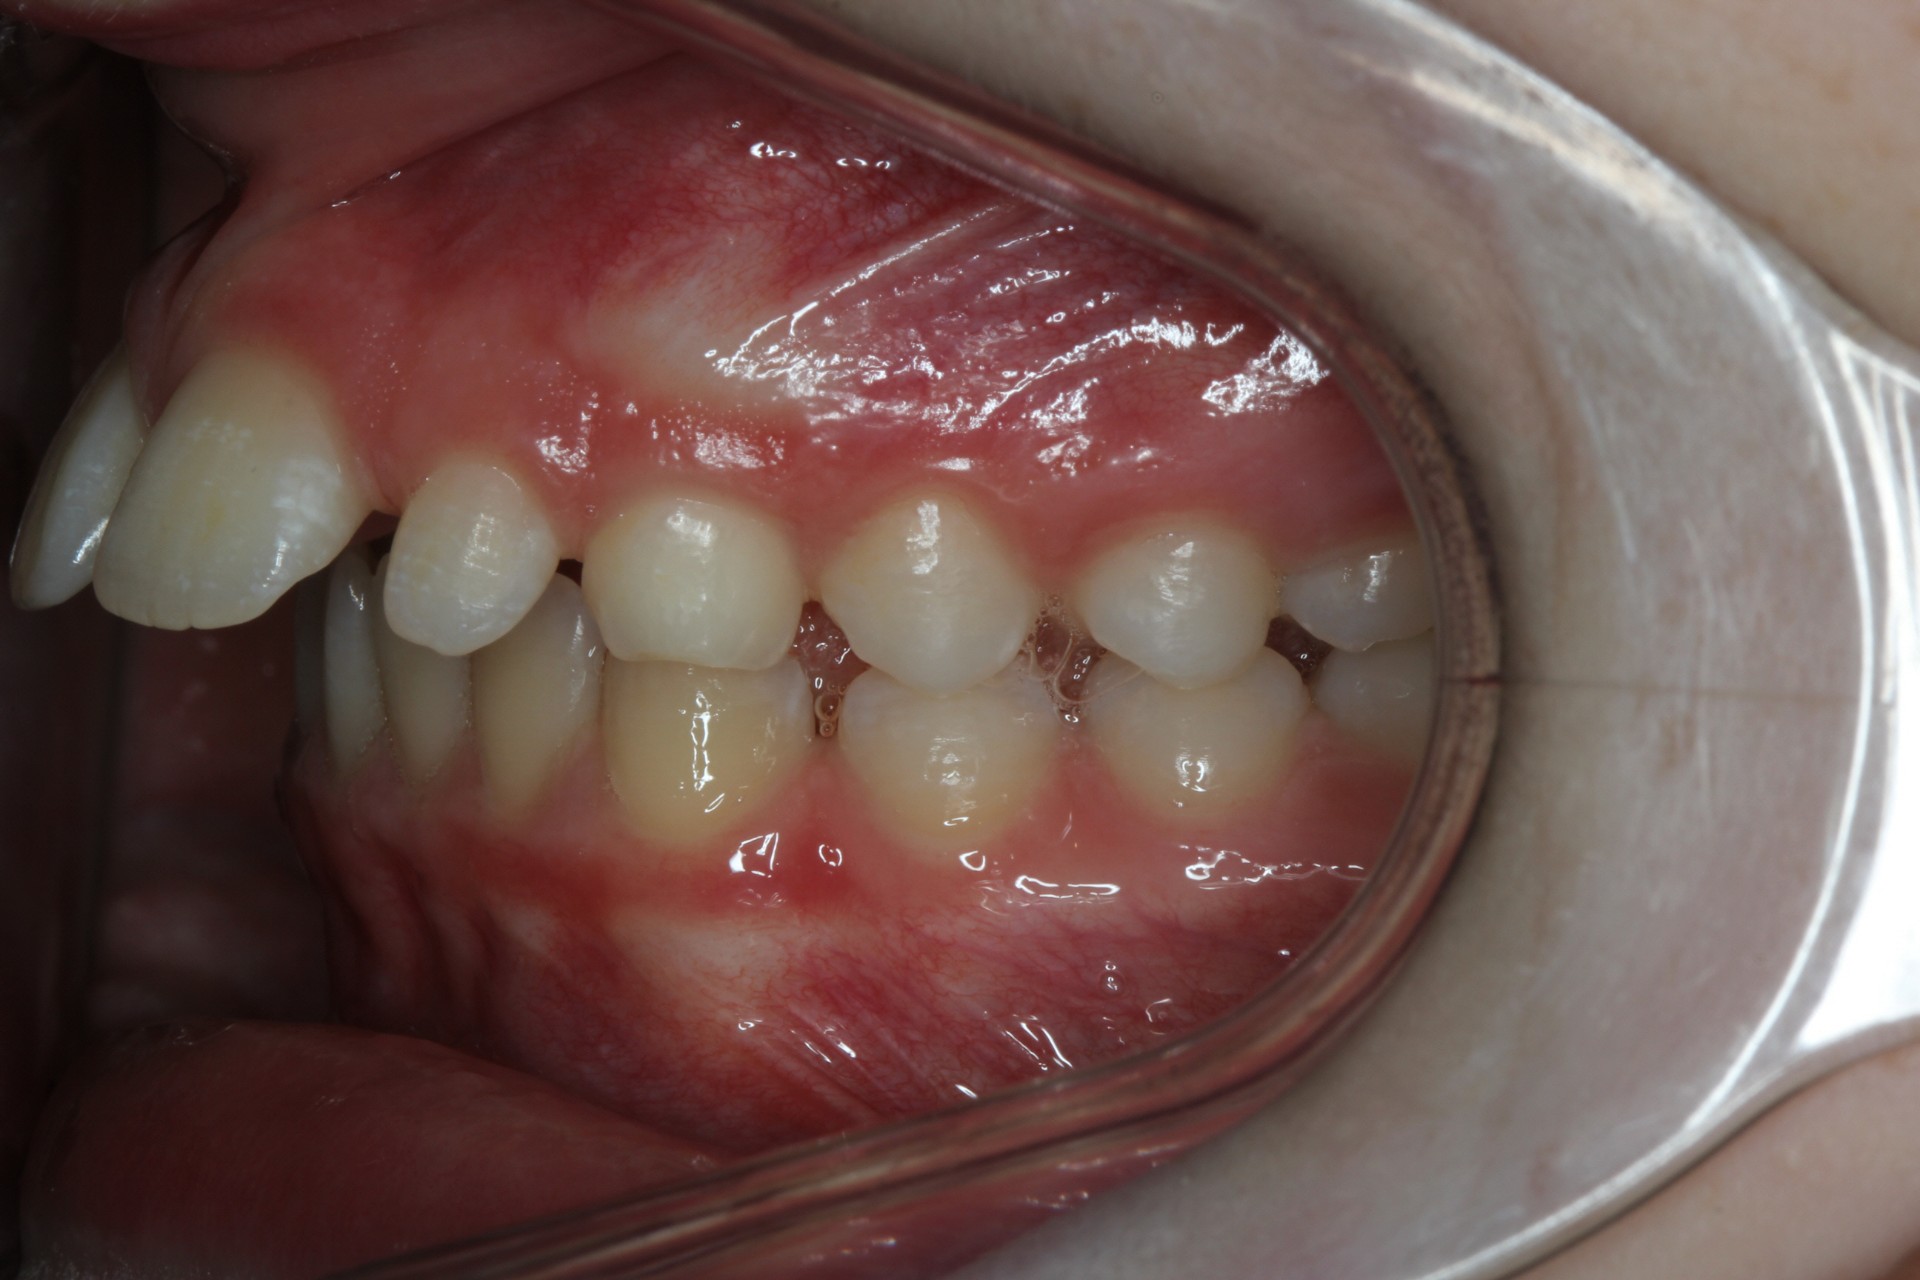

Protruding front teeth and spacing – Child case